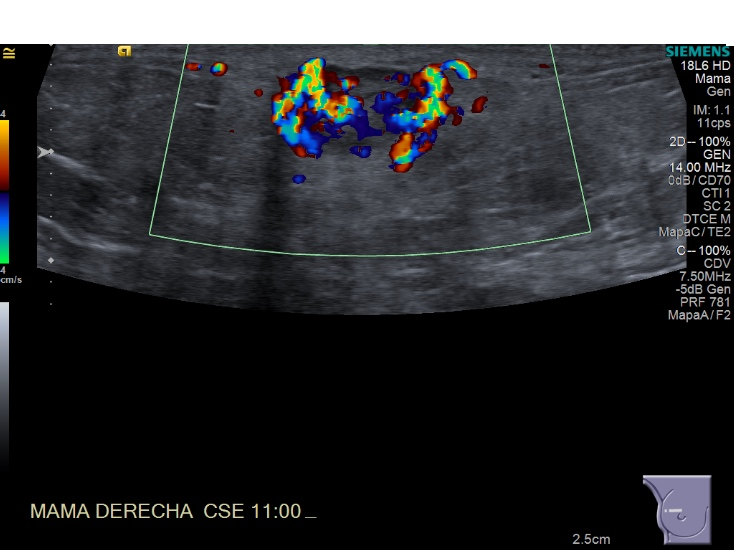

Crioablacion de tumor en mama derecha